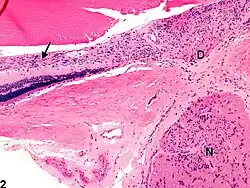

Gliosis

D - disco visual

N - nervio óptico

Los astrocitos son células gliales de gran tamaño y con variadas funciones, incluyendo la acumulación en regiones donde ha habido daño de neuronas. La hiper-proliferación de estos componentes celulares de la neuroglía es el signo histopatológico más importante de un daño al SNC. Los astrocitos pasan por un proceso de hipertrofia e hiperplasia, el núcleo celular aumenta de tamaño y se vuelve vesicular con nucléolos prominentes. El citoplasma, que una vez fuera difuso, se expande y se vuelve brillante bajo la tinción celular e irregular en su morfología, del cual parten numerosos procesos llamados astrocito gemistocítico.